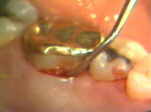

Note la

inflamación gingival y la presencia de placa supragingival en los

dientes. En bucal del segundo molar hay una bolsa profunda al

sondaje y placa supra y subgingival al movimiento lateral de la sonda. |

| Aquí puede verse la

permanencia de cálculo al separar con aire el tejido gingival. Este cálculo está

muy alejado para ser eliminado por un instrumento ultrasónico o un instrumento de

mano. Los estudios han mostrado que es prácticamente imposible quitar todo el cálculo

subgingival. A pesar de esto en la mayoría de los casos los tejidos sanan

satisfactoriamente con un tratamiento subgingival cuidadoso. |